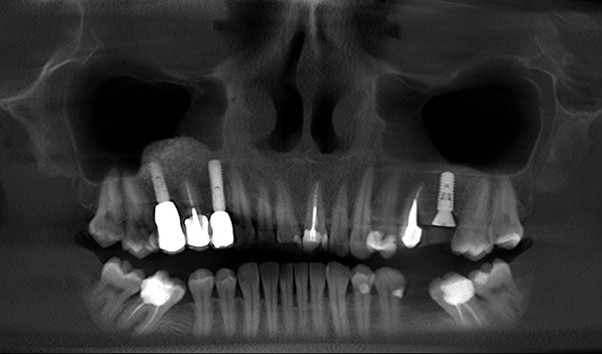

The increasing demand for efficient and minimally invasive tooth replacement options has driven the adoption of immediate implant placement. Within the framework of a patient-centered and comprehensive treatment plan, selecting the appropriate timing for implant placement is a crucial determinant of overall treatment success. Unlike delayed implant placement, which requires several months of healing after extraction, IIP involves placing the implant directly into the fresh extraction socket (Figures 1 and 2). This technique not only reduces the number of surgical interventions and associated patient morbidity but also allows for immediate implant-supported fixed restorations if conditions permit. It significantly reduces both chair time and overall treatment duration compared to other protocols (Puisys et al., 2022). Advances in surgical protocols, digital diagnostics, and implant design have made IIP increasingly predictable, particularly when combined with immediate temporization. However, the clinician must weigh these benefits against the increased technical demands and biological complexities inherent in the procedure. The ITI SAC Classification Tool (Straightforward, Advanced, Complex) helps stratify cases by risk and complexity, thereby guiding appropriate case selection and operator readiness (Morton et al., 2023).

Fig. 1a: CBCT of initial situation with non-restorable tooth 21